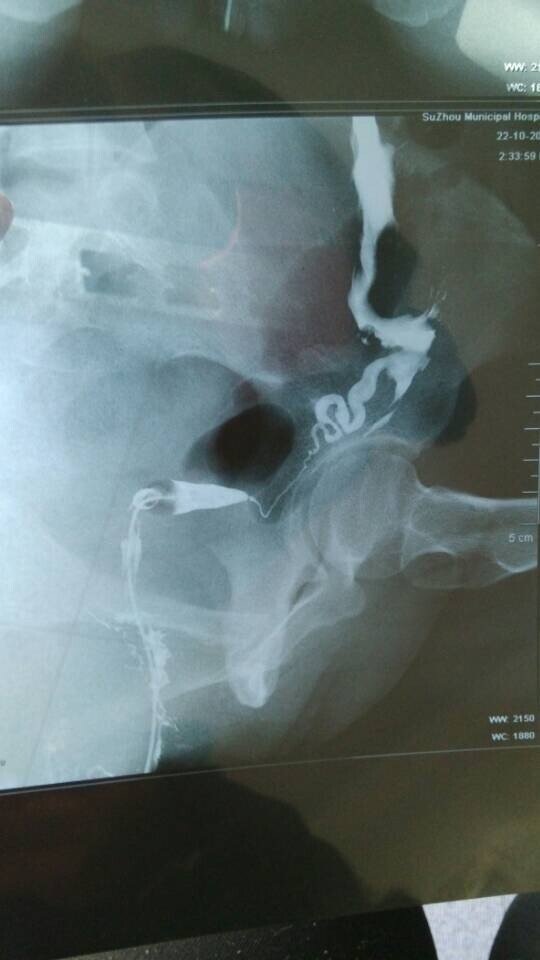

输卵管造影显示一侧不通,做宫腹腔镜成功率多大? 结婚一年未孕,14年10月份做了输卵管造影,显示右侧不通,所以医生建议做宫腹腔镜,但是我在网上查到说这个手术不是所有的都能疏通,而且要全身麻醉,副作用较大,还会感染炎症,我本身有霉菌性阴道炎,且在11年有做过一次人流,想请哪位专家帮我看看我这个情况做这个手术右侧疏通的几率多大、这个手术真的成功率很低吗?我该怎么办?而且连续两个月堵的那一侧在排卵,我可不可以打促排卵的药促使两边都排卵?还有输卵管上举做人工是不是会宫外孕啊??问题很多,多谢各位专家了 点击展开 匿名用户 2015-01-04 15:14 推荐回答 你好,做腹豆柴腔镜手术比较好一点,让自己自然怀孕比较好,做人工受精成功率也不是很高的而涌渐神且畸形率比较唉究大。 cn#BfuaaGVkLG 2015-01-05 14:58 宝宝知道提示您:回答为网友贡献,仅供参考。 相关问题 输卵管近端堵塞;用宫腹腔镜手术成功率多少?求专家指点都快离婚了因为不孕 输卵管造影多久可以做宫腹腔镜 输卵管不通做了宫腹腔镜手术已经快一年了,还未孕,还用再做造影检查吗

结婚一年未孕,14年10月份做了输卵管造影,显示右侧不通,所以医生建议做宫腹腔镜,但是我在网上查到说这个手术不是所有的都能疏通,而且要全身麻醉,副作用较大,还会感染炎症,我本身有霉菌性阴道炎,且在11年有做过一次人流,想请哪位专家帮我看看我这个情况做这个手术右侧疏通的几率多大、这个手术真的成功率很低吗?我该怎么办?而且连续两个月堵的那一侧在排卵,我可不可以打促排卵的药促使两边都排卵?还有输卵管上举做人工是不是会宫外孕啊??问题很多,多谢各位专家了